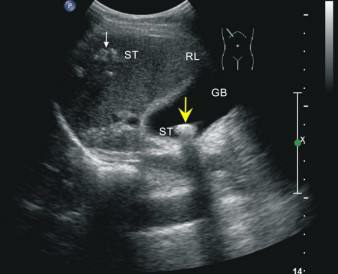

難得一個(gè)比較平靜的夜班,我正在辦公室寫(xiě)病歷,突然聽(tīng)到一陣急促的腳步聲傳來(lái),我馬上跑到護(hù)理站就見(jiàn)一位50歲左右的先生,由一群家屬推著平車而來(lái),我馬上叫護(hù)士把患者安排進(jìn)了監(jiān)護(hù)室。這位先生姓錢(qián),自訴飲酒后出現(xiàn)胸骨后疼痛4小時(shí),呈壓榨性,持續(xù)不緩解,伴大汗、面色蒼白、惡心、欲吐,既往無(wú)高血壓、糖尿病、冠心病病史,吸煙史30年,偶有飲酒,入院時(shí)查體血壓為120/80mmHg,心率:98次/分,節(jié)律規(guī)整,未聞及明顯雜音。心電圖:竇性心律,心率98次/分,II、III、aVF導(dǎo)聯(lián)病理性Q波,ST段下移,不正常心電圖。不除外急性心肌梗死。急檢心肌酶及超敏肌鈣蛋白、淀粉酶,結(jié)果回報(bào)心肌酶、超敏肌鈣蛋白無(wú)明顯改變。疼痛時(shí)復(fù)查心電圖較前無(wú)變。胸痛癥狀仍持續(xù)不緩解,給予曲馬多止痛不改善。請(qǐng)示李桂武主任醫(yī)師,主任給予詳細(xì)詢問(wèn)病史、癥狀及查體,患者膽囊區(qū)有壓痛無(wú)反跳痛,考慮患者可能存在膽囊性疾病,不排除腎結(jié)石,指示:急檢肝膽胰脾彩超及泌尿系彩超。我急忙陪著患者及家屬去門(mén)診彩超室做肝膽胰脾及泌尿系彩超。結(jié)果如下圖。提示膽囊結(jié)石。

請(qǐng)肝膽外科梁博主任會(huì)診后建議行CT檢查以進(jìn)一步明確診斷,肝膽胰脾CT結(jié)果可見(jiàn)膽囊不大,內(nèi)見(jiàn)高密度結(jié)節(jié),約10mm(IM33),膽總管無(wú)擴(kuò)張。建議轉(zhuǎn)入肝膽外科行手術(shù)治療。